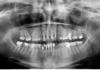

pawa Опубликовано 6 августа, 2010 Поделиться Опубликовано 6 августа, 2010 Добрый день, посоветуйте, что можно сделать с 4-мя верхними и нижними передними зубами. Заранее спасибо.В нижних резцах напрягает отсутсвие пломбировки каналов и анкера. Имхо. Ссылка на комментарий

Грецкий орех Опубликовано 6 августа, 2010 Автор Поделиться Опубликовано 6 августа, 2010 Там еще и кисты давнишние на корнях. Нижние зубы сломались еще в школьные годы, несколько раз восстанавливались на штифтах. Ссылка на комментарий

pawa Опубликовано 6 августа, 2010 Поделиться Опубликовано 6 августа, 2010 (изменено) Между 17 и 15 в пазухе какая то хрень выросла! Нужно КТ делать, под вопросом интрасинусальная киста.http://s53.radikal.ru/i140/1008/34/8ea494b5282d.jpg Изменено 6 августа, 2010 пользователем pawa Ссылка на комментарий

pawa Опубликовано 6 августа, 2010 Поделиться Опубликовано 6 августа, 2010 у меня там зуб был удален очень давно. все равно выросла?то что зуб удалён это понятно, а вот тень нехорошая, надо разобраться. Ссылка на комментарий

pawa Опубликовано 6 августа, 2010 Поделиться Опубликовано 6 августа, 2010 Чем эта киста опасна? Мне одну удаляли, на переднем зубе. Это что-то похожее или у кист тоже есть разновидности? Пожалуйста, ну хоть кто-нибудь, посоветуйте, что с передними зубами делать, про жевательные я все поняла уже!!!!Фото бы посмотреть. Е-мах коронки очень красиво смотрелись бы на 12, 11, 21, 22 зубах. Ссылка на комментарий

pawa Опубликовано 6 августа, 2010 Поделиться Опубликовано 6 августа, 2010 (изменено) Фото бы посмотреть.Е-мах коронки очень красиво смотрелись бы на 12, 11, 21, 22 зубах.Расширение как минимум от 13 до 22 и от 44 до 34.Но эти рекомендации могут быть изменены ( отменены) после гипсовки диагностических моделей в артикуляторе. Изменено 6 августа, 2010 пользователем pawa Ссылка на комментарий